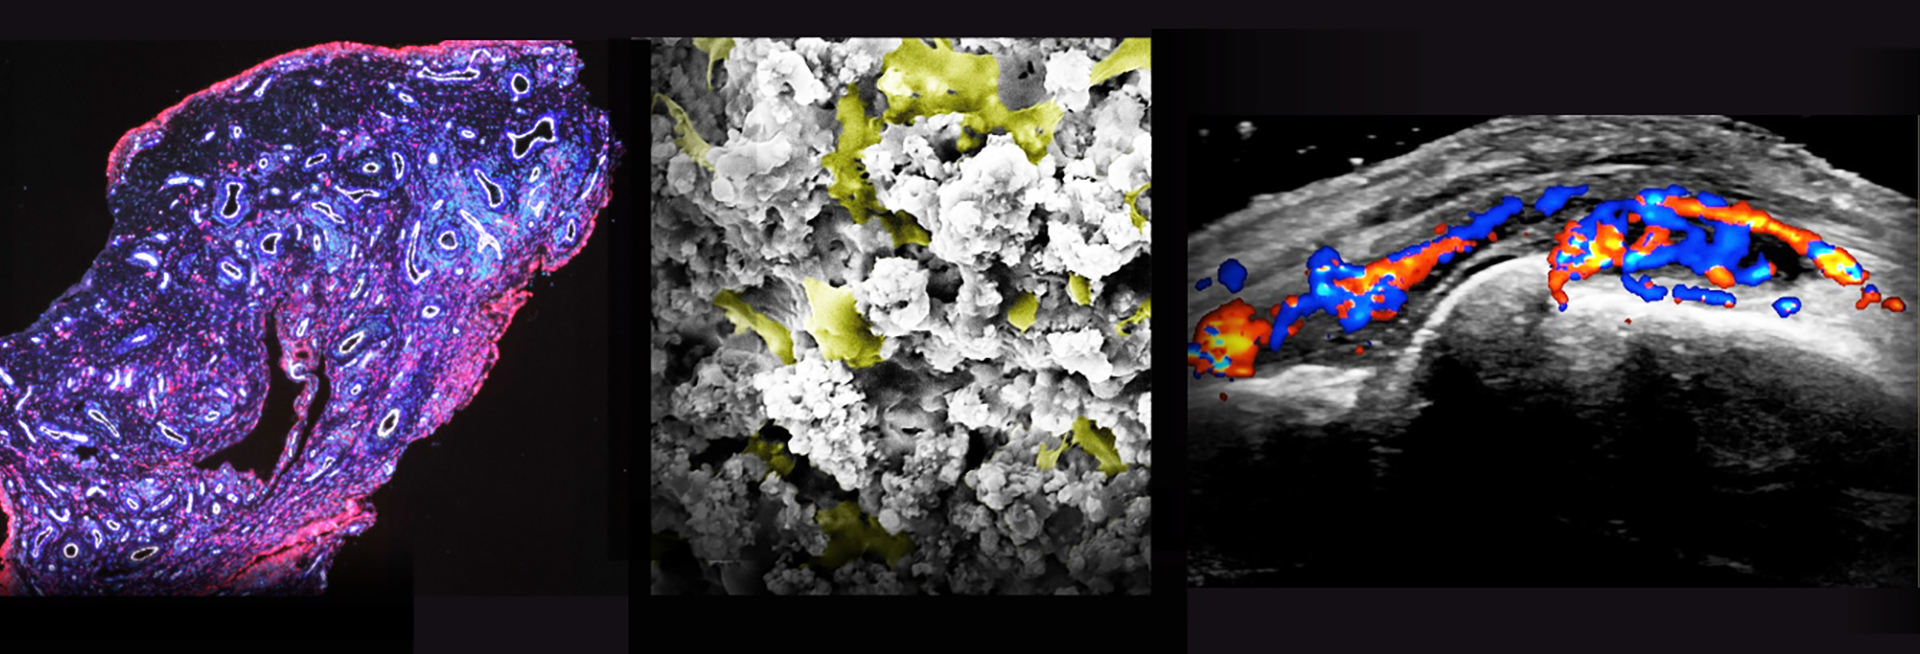

Our research has a major focus on inflammatory rheumatic diseases; in particular the pathobiology, comorbidity and patient reported outcomes associated with rheumatoid arthritis, Sjögren’s syndrome and systemic lupus erythematosus, as well as their epidemiology and clinical management. We are a substantial multidisciplinary team including academic/clinical rheumatologists, general practitioners, biological/behavioural scientists, allied health professionals and patient research partners.

Hear from our experts and patients about ultrasound-guided biopsies and latest research.